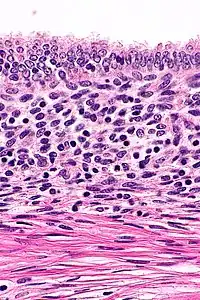

The most common imaging techniques include ultrasound, computed tomography (CT), and MRI. Intravenous pyelography (IVP) has also been used in some cases to assess for possible congenital anomalies of the kidneys.[3] The appearance of these rare tumors on diagnostic imaging has not been extensively described, and in each case documented in the literature, the diagnosis was ultimately made after surgical removal using histologic analysis.[3]

On microscopic examination, patterns of smooth muscle and endometrial tissue must be assessed with care to differentiate adenomyomas from masses of similar appearances, such as endometriosis containing smooth muscle and leiomyomas containing endometriosis.[3]